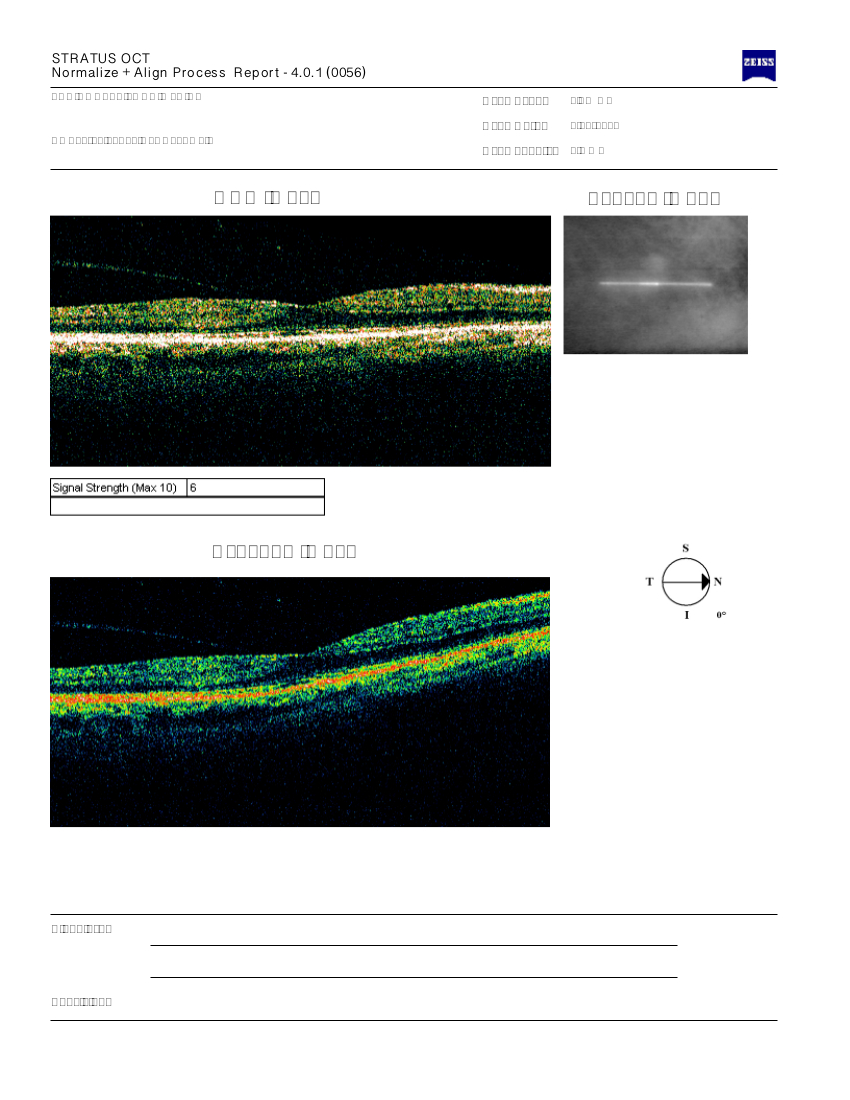

Effettuato OCT maculare: si evidenzia nell’occhio destro un’importante sindrome dell’interfacies vitreo retinica con pucker maculare e sospetto foro in formazione, aumentato spessore retinico maculare e schisi. L’occhio sinistro ha un profilo maculare nella norma.

Consigliato e programmato intervento chirurgico di vitrectomia e peeling della membrana epiretinica maculare nell’occhio destro.

Effettuato OCT (vedi allegato): occhio destro nella norma, occhio sinistro: si evidenzia un pucker maculare.

In considerazione del calo del visus delle metamorfopsie e della conferma dell'esistenza del pucker maculare sia all'esame del fundus sia all'OCT si consiglia intervento di vitrectomia e peeling maculare (asportazione della membrana epiretinica maculare).

OCT: confermato distacco sieroso occhio sinistro (vedi allegato)

Programmato OCT (vedi allegato): si conferma l'esistenza di un pucker maculare nell'occhio destro

Effettuato OCT (vedi allegato): nell'occhio sinistro si evidenzia un foro maculare con trazione vitreo retinica. Le dimensioni del foro maculare inferiore ai 400 micron e le caratteristicahe di trazione vitreo retinica suggeriscono la possibilità di utilizzare l'ocriplasmina intravitreale.

Effettuato OCT (vedi allegato): confermato il sospetto diagnostico di edema maculare cistoide (sindrome di Irvine e Gass) e iniziale sindrome dell'interfacies vitreo retinica